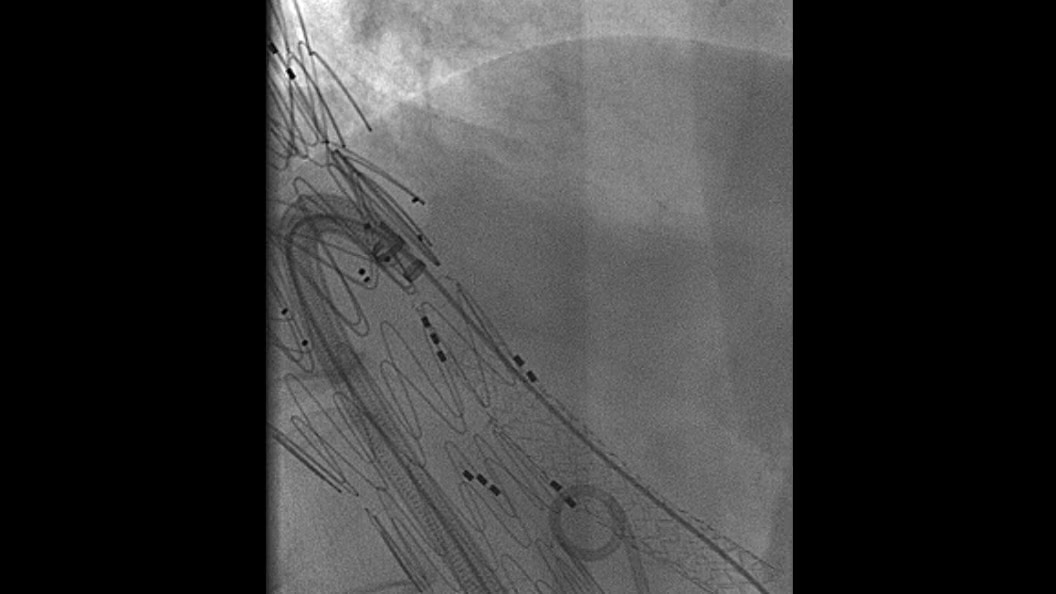

EVAR ASSIST

Perform endograft procedures in one go with intuitive tools and a simplified workflow - less radiation, more efficiency